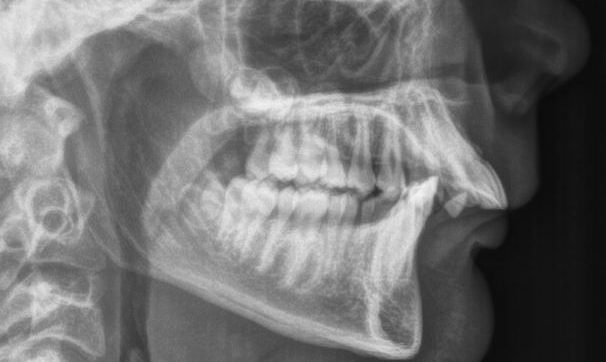

Jaw Surgery